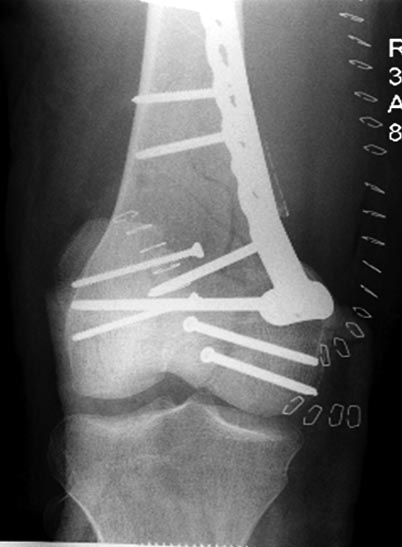

Раны в области коленного сустава и на плече до сих пор чистые, остаются

открытыми. Отсутствует признаки инфекции, решили превратить недостаток в

преимущество, т.е. фиксировать через открытые раны пластинами.

На 9й день фиксация дистального бедра, где фрагмент Hoffa и вертикальный

перелом надколенника, зафиксированы винтами.